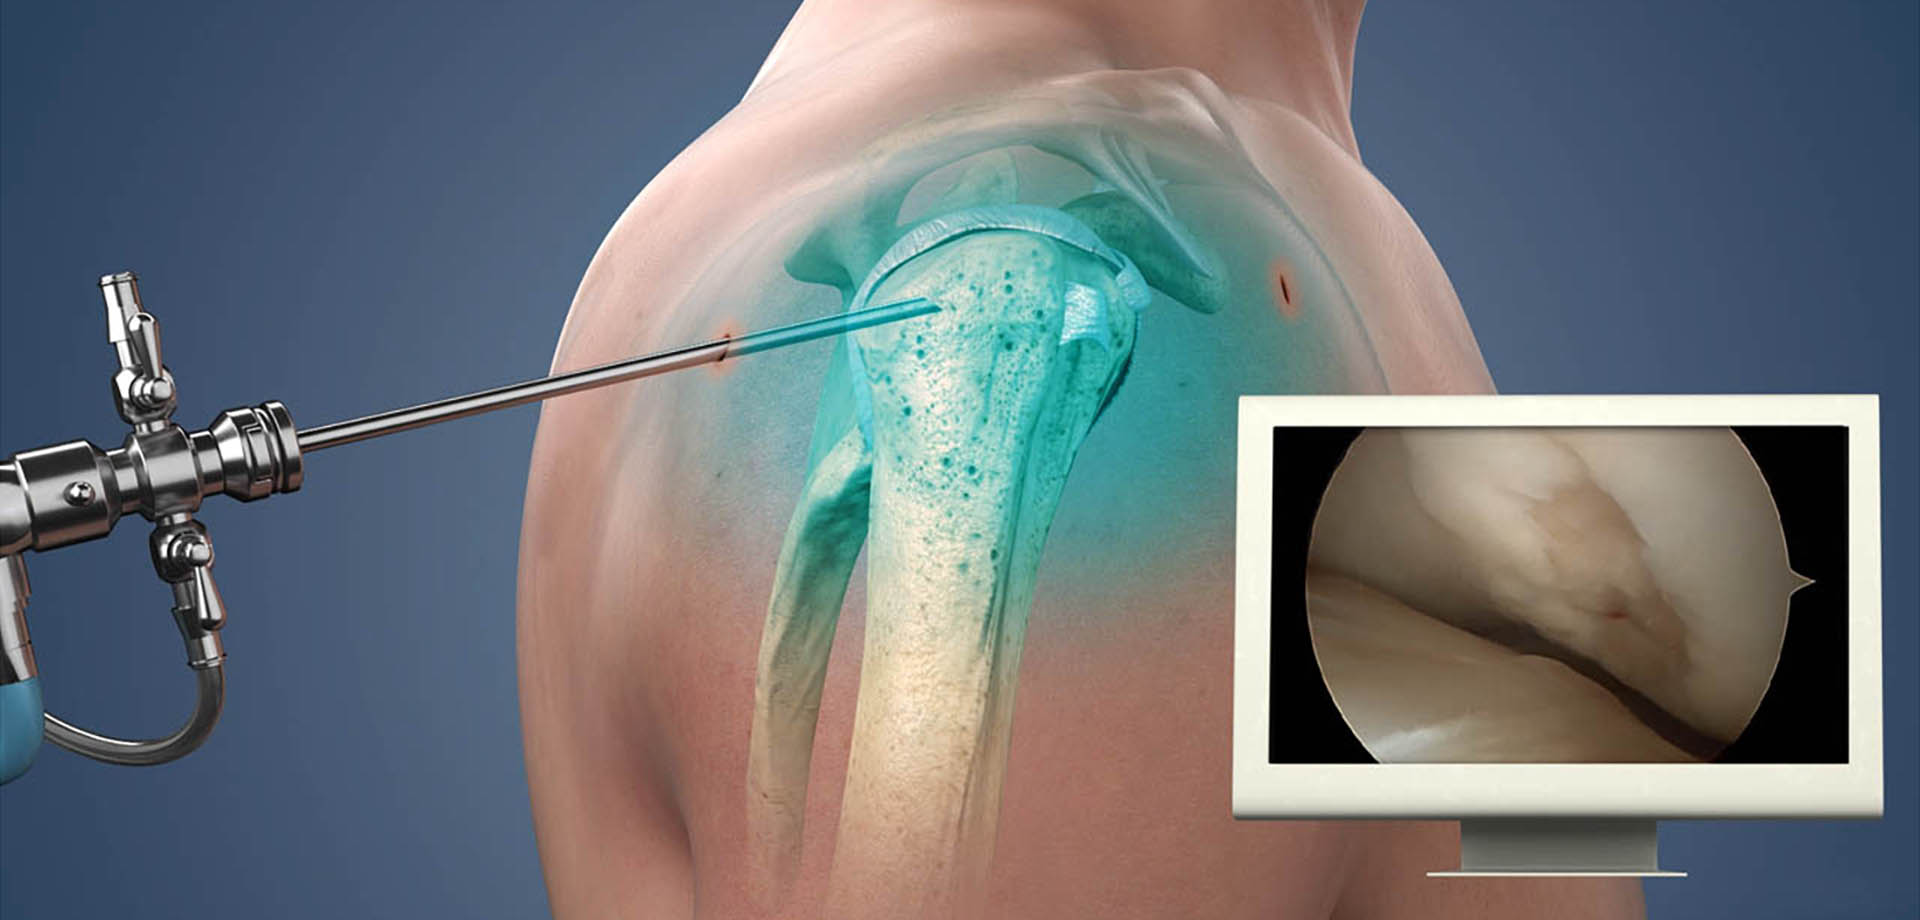

The department offers a full spectrum of non-surgical and surgical orthopedic services, with a strong emphasis on minimally invasive techniques. Advanced procedures such as arthroscopy, minimally invasive and endoscopic spine interventions, and modern fracture fixation methods are used to reduce surgical trauma, minimize pain, and promote faster recovery with shorter hospital stays. These approaches allow patients to return to daily activities and work more quickly, while maintaining high standards of safety and clinical outcomes.

Sports medicine is an integral component of the department’s services. We manage acute injuries, overuse conditions, and degenerative joint problems commonly seen in athletes and physically active individuals. Conditions involving the knee, shoulder, ankle, hip, and spine are treated through a coordinated approach that combines medical management, targeted rehabilitation, and, when necessary, surgical intervention. Rehabilitation programs are carefully structured to restore strength, flexibility, balance, and performance while reducing the risk of re-injury.